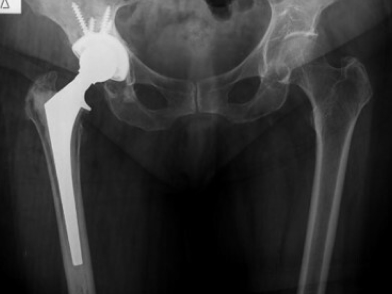

Η διάγνωση της περιπροθετικής χαλαρωσης περιλαμβάνει συνδυασμό κλινικού, απεικονιστικού και μερικές φορές εργαστηριακού ελεγχου. Οι απεικονιστικές μελέτες που χρησιμοποιούνται συνήθως είναι: